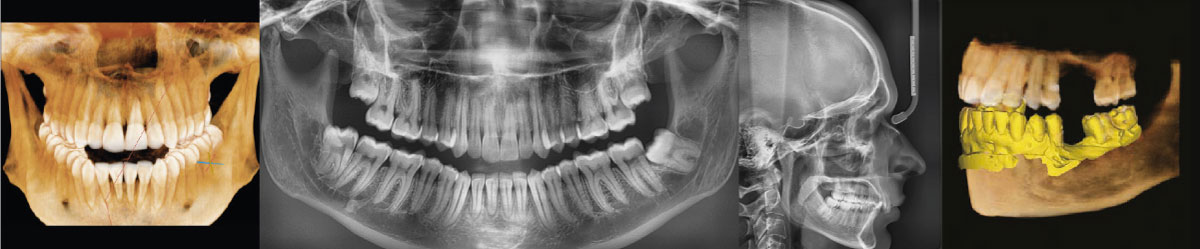

Новый шаг в развитии панорамной визуализации с Insight pan

Компьютерный томограф Green 16 от Vatech может снимать многослойное панорамное изображение, называемое Insight Pan, которое обеспечивает визуализацию в глубину панорамы. Поскольку у каждого пациента форма зубных рядов и наклон зубов могут отличаться, традиционные панорамные изображения могут иногда пропускать важные детали, которые оказываются за пределами единственного фокального слоя. Функция Insight Pan служит для получения многослойных панорамных изображений, гарантирующих возможность наблюдать необходимую анатомию на нужной глубине.

• • Скрытые корни и каналы

• • Расположение пульпы и гуттаперчи

• • Перелом корня или сломанный файл

• Insight Navi

Insight Navi в программе EzDent-i — это специальная функция для аппарата Green 16. Она позволяет получить информацию о внутренних структурах послойно перемещаясь на панорамном снимке вперед-назад.